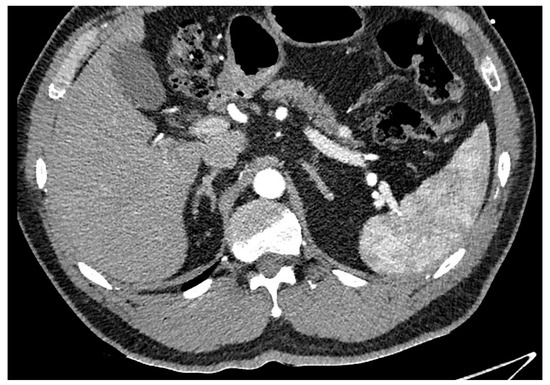

Pancreatic neuroendocrine tumours (PaNET) are classified into 2 broad groups: hormone-secreting (functional) or non-secreting (non-functional) tumours. Insulinomas and gastrinomas are the most common types of functioning tumours. Non-functioning tumours that are smaller than 2 cm are usually managed with surveillance until they measure more than 2 cm, which is regarded as a critical size. See Figure 6. Depending on the anatomical location of the primary, they can be managed with Whipples resection, distal or total pancreatectomy. See Figure 7 Functional tumours smaller than 1 cm may be treated with enucleation of the tumour, leaving as much as possible of the pancreatic parenchyma intact.

Figure 6. CT arterial phase with lesion in the tail of the pancreas consistent with neuroendocrine tumour.